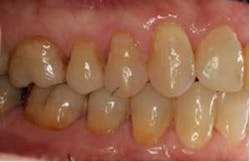

SFOT was used with a high-tech clear aligner to address hard- and soft-tissue deficiencies and severe maxillary and mandibular arch constriction.

Total treatment time: 6 months. Patient declined recommended further clear aligner refinement and fine-tuning periodontal plastic surgery.